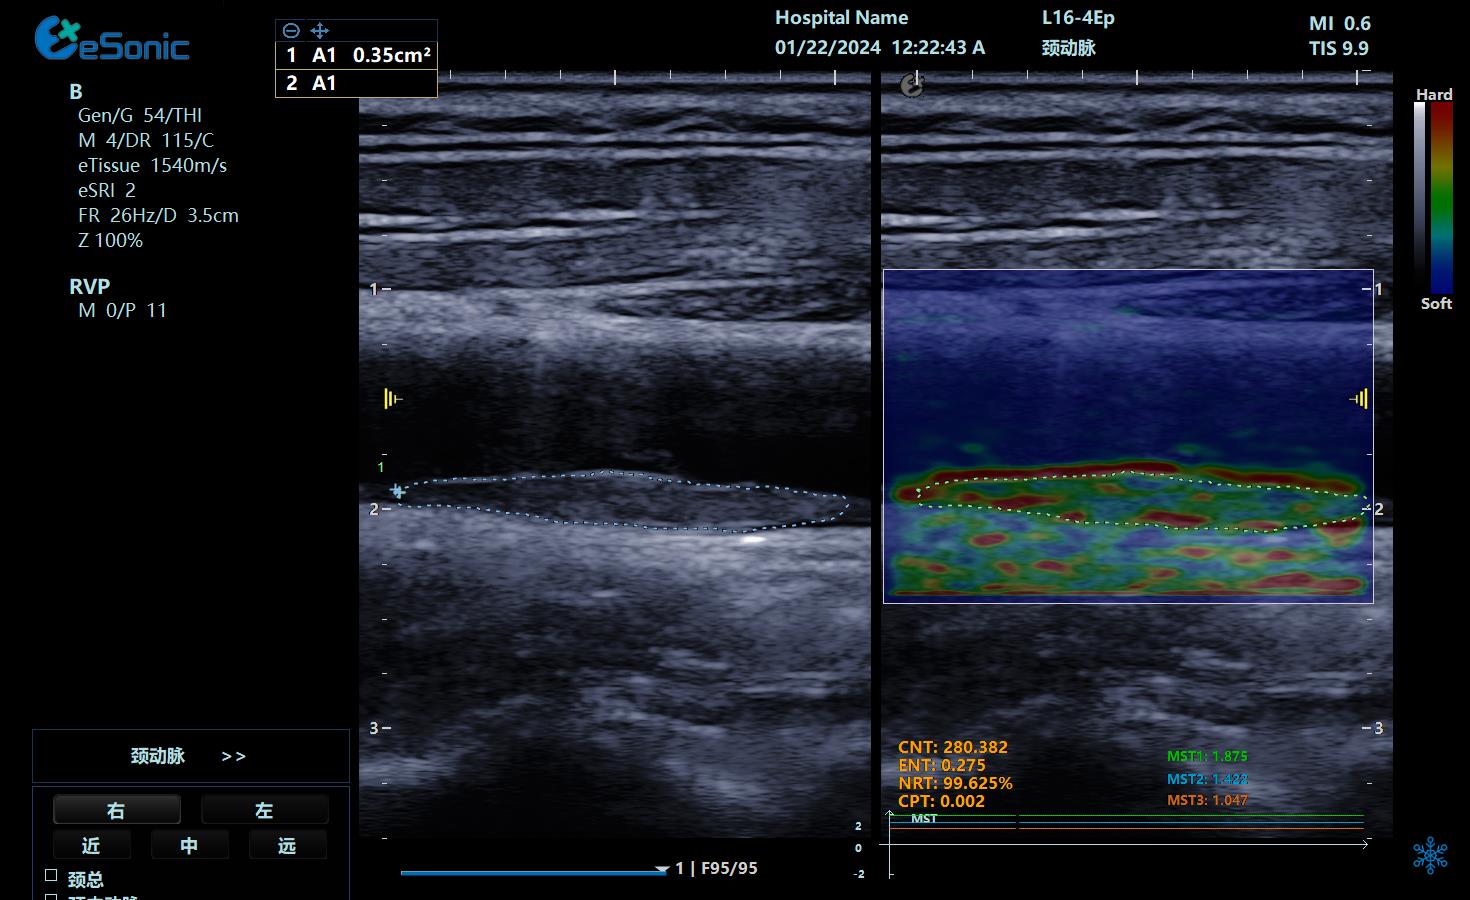

颈动脉不稳定斑块